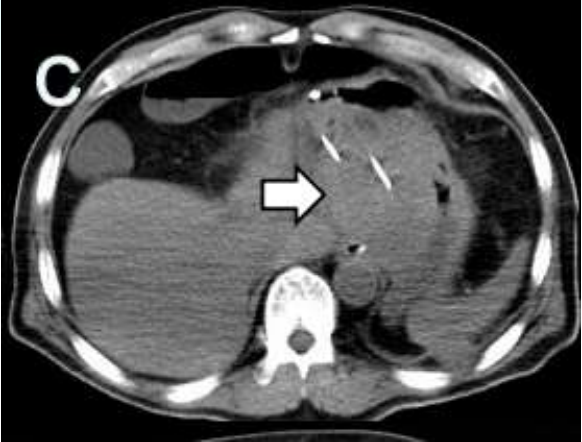

術(shù)中通過CT定位,聯(lián)合彩色超聲引導(dǎo)穿刺,分別經(jīng)腹,經(jīng)左側(cè)胸壁進(jìn)針。2支消融針間隔2.5cm且互相平行,消融針針尖暴露2cm,開始進(jìn)行消融。因肝臟腫瘤體積較大,對(duì)腫瘤分區(qū)進(jìn)行多次消融,確保消融范圍能完全覆蓋。

術(shù)中操作

復(fù)查結(jié)果

術(shù)后1周和術(shù)后2月復(fù)查腹部CT均提示:肝臟及左側(cè)腹膜腫瘤可見大片狀低密度壞死區(qū),肝臟腫瘤外周有少許強(qiáng)化灶。心電圖及心肌酶未見明顯異常,腫瘤標(biāo)志物指標(biāo)顯著下降?;颊叩捏w重較術(shù)前上升4kg,疼痛程度及日?;顒?dòng)能力較前明顯改善。

術(shù)后復(fù)查:左為術(shù)后1周,右為術(shù)后2月